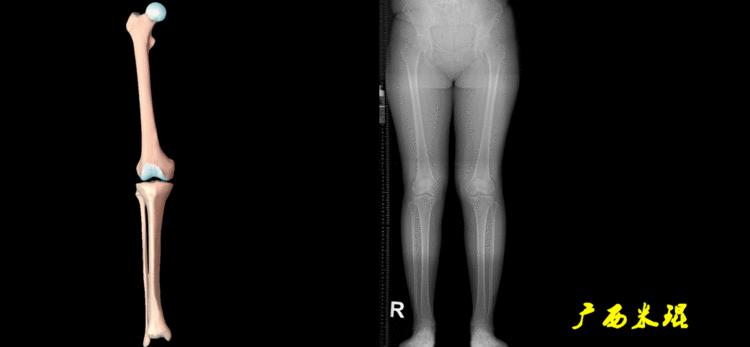

解剖胫骨近端外侧角(也叫aMPTA):胫骨干上段轴线与胫骨平台切线(关节线)在膝关节外侧所形成的夹角,常称为胫骨角,正常为87°±3°。大多数膝内翻患者的畸形发生于胫骨上端,表现为胫骨角大于90°。严重的膝内翻畸形发生在整个下肢,股骨干及胫骨干都有可能形成向内弯曲的弧形。

最常见的下肢畸形发生于冠状面,即膝内外翻畸形,冠状面的对线异常通过应用“对线异常检验”进行分析,机械轴的偏移(MAD)表现为对线异常。

膝内翻是指下肢力线通过膝关节中心点内侧,距中点2mm以上,偏内超过15mm为显著膝内翻。膝外翻是指下肢力线通过膝关节中心点外侧,距中点2mm以上,偏外超过10mm为显著膝外翻。